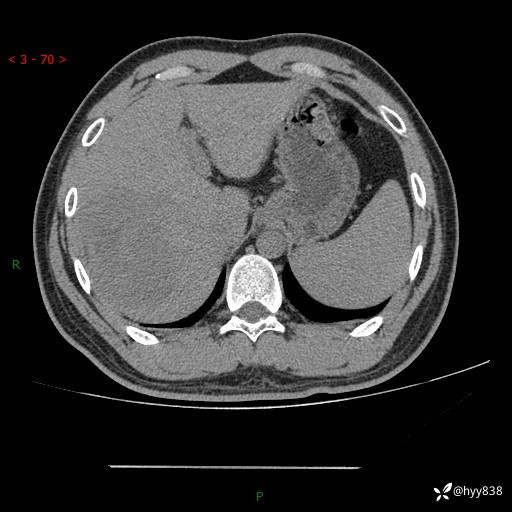

患者性别:男

患者年龄:29岁

简要病史:外院超声提示肝脏占位性病变

辅助检查:CT

临床诊断:肝占位

肝脏CT平扫